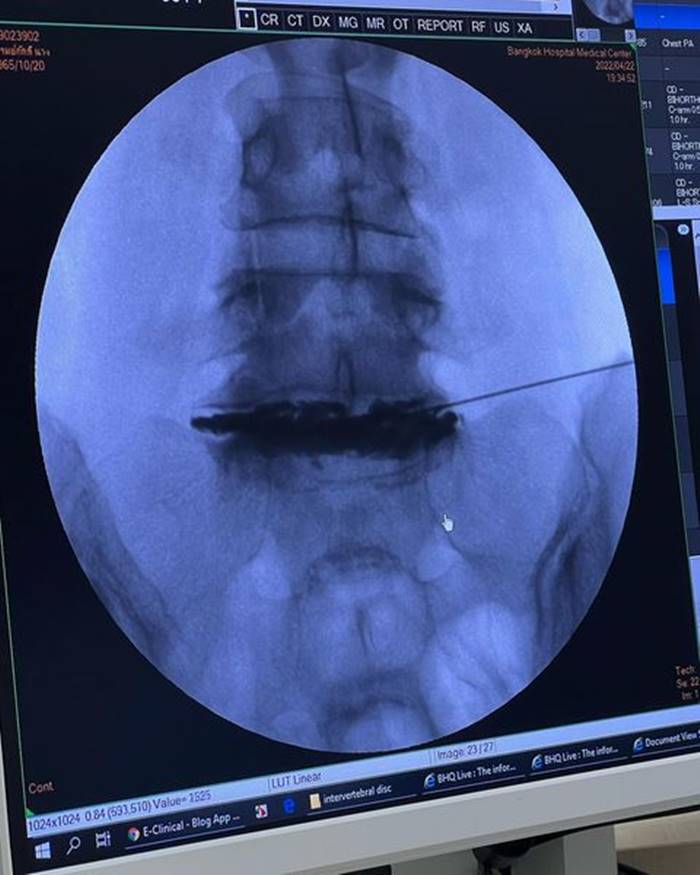

อยากขอเตือนเพื่อนๆ นะคะ ว่าถ้าออกกำลังท่าไหนแล้วรู้ตัวว่าไม่ไหวก็ให้บอก trainer ค่ะ อย่าฝืนทำ เพราะลงท้ายอาจจะต้องผ่าตัดแบบหนุ่ย.. trainer ให้ทำ Squat ที่หนุ่ยก็หันไปบอกแล้วว่าหนักไปทำไม่ได้ เค้าก็ยังให้ทำ ผลคือหมอนรองกระดูกปลิ้น ต้องผ่าตัดใส่เหล็กตามภาพเลยค่ะ..ตอนนี้ก็ต้อง slowlife ไป 4-5 เดือน”